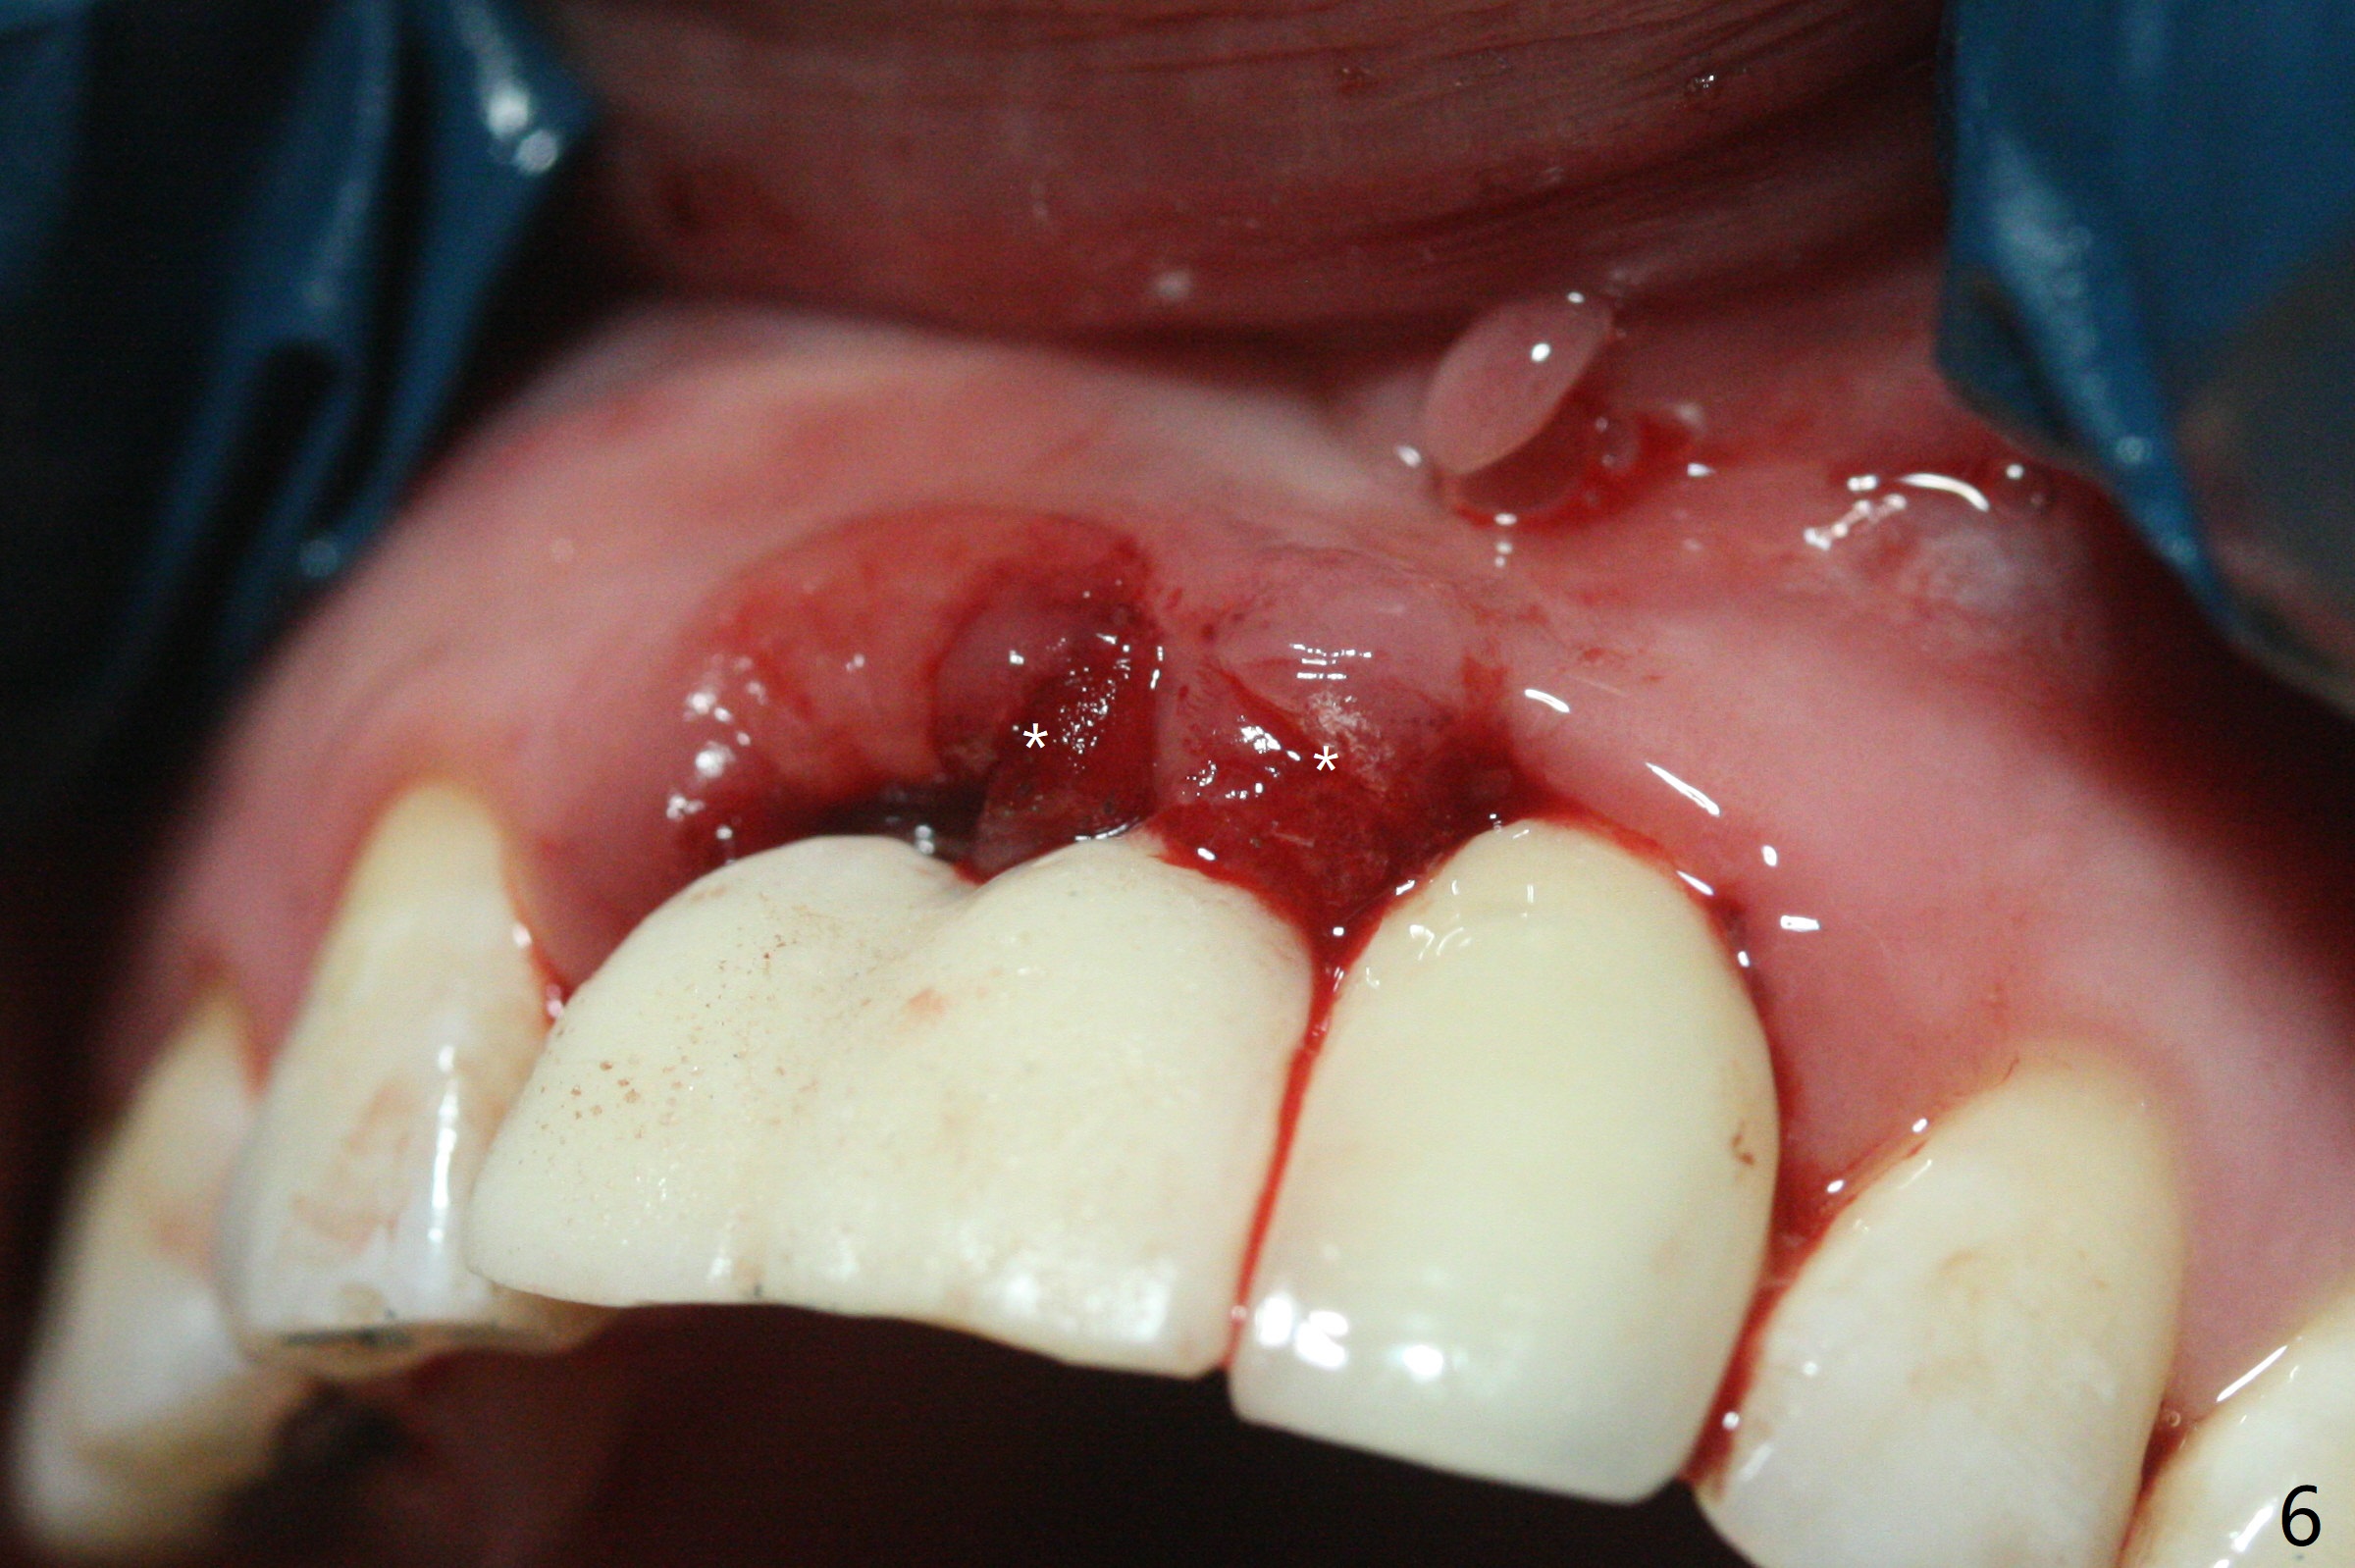

拆除部分桥发现:中,侧切牙牙龈红肿(图一),不利于切口和伤口愈合。不过还是在中切牙区切开,牙龈相当厚,有利于今后牙龈形成凹陷和乳头。坏消息是近远中距离太短,不利于植牙以及今后局部卫生维护,所以决定只在侧切牙种植(图二,三),完成钻洞后,颊侧根尖穿孔植骨,然后植入植体,即刻放置修复基台(图四 (*:牙龈乳头)),暴露基台牙龈缘,制作临时悬臂桥 (图五),两个中切牙牙冠长度差不多,插入临时桥时颊侧牙龈乳头基本形成(图六:*),缝合前颊侧,腭侧牙龈瓣下放置粘性骨块(图七,八:* )和PRF膜(图七:^)。最后使用牙周敷料。但愿术后牙龈炎症消失,形成良好牙龈乳头和pontic concavity。 其实由于口腔卫生习惯,术后十七天颊侧牙龈仍红肿(图九),而腭侧正常。如果口腔卫生改善而红肿依然存在,让实验室制作临时桥。术后一个月颊侧牙龈红肿好些(图十),好像骨粉丢失少许,可能与水枪使用有关。右上1牙冠显得太短(*)。也太肥大,因为右上1切缘太颊侧,与左上1对比(图十一:*)。由于颊侧牙龈(图十二:B)术中推向颊侧,与腭侧(P)牙龈之间放置大量粘性骨粉,术后一个月骨粉(<)形成牙龈,形成凹陷。颊侧萎缩不再明显了。右上1牙冠颈部多加些树脂,牙齿就显得长的多(图十三:箭头)。与侧切牙之间颈部故意留下间隙(*),让牙龈入位(空箭头),形成龈乳头。当右上1临时牙冠切缘(图十四:*)移到腭侧,外形改观不少。下次改善侧切牙唇侧。术后两个月三个星期牙龈红肿好像减轻,牙龈没有进入切牙间隙,干脆用树脂关闭(图十五:> <)。下次减少侧切牙切缘(^),适当增加中切牙长度(上提牙龈)。术后3.5个月植体好像整合,基台完全就位(图十六)。术后3.5个月Pontic凹陷形成,但是1,2之间龈乳头始终无法形成(图十七)。以后类似病例应该多种植一个。此例草率取模,可能需要临时粘固,观察植体近中颊侧所谓瘘道,必要刮治。由于比色不佳,需要实验室颜色更改,病人强化卫生,术后七个月,永久性牙冠粘固前,局部牙龈健康(图十八)。